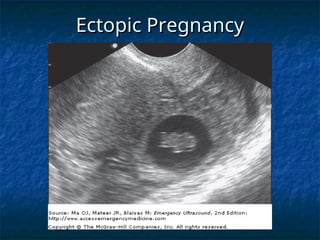

Ectopic Pregnancy

Ectopic Pregnancy – A surgical

emergency of pregnancy

 The leading cause of first trimester

The leading cause of first trimester

maternal death

A heterotopic pregnancy (to

compare normal vs. abnormal)